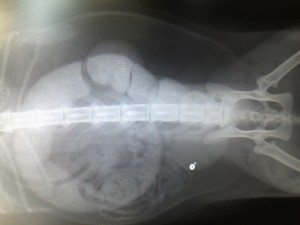

来院時のレントゲン写真 大腸いっぱいに便がつまってます!